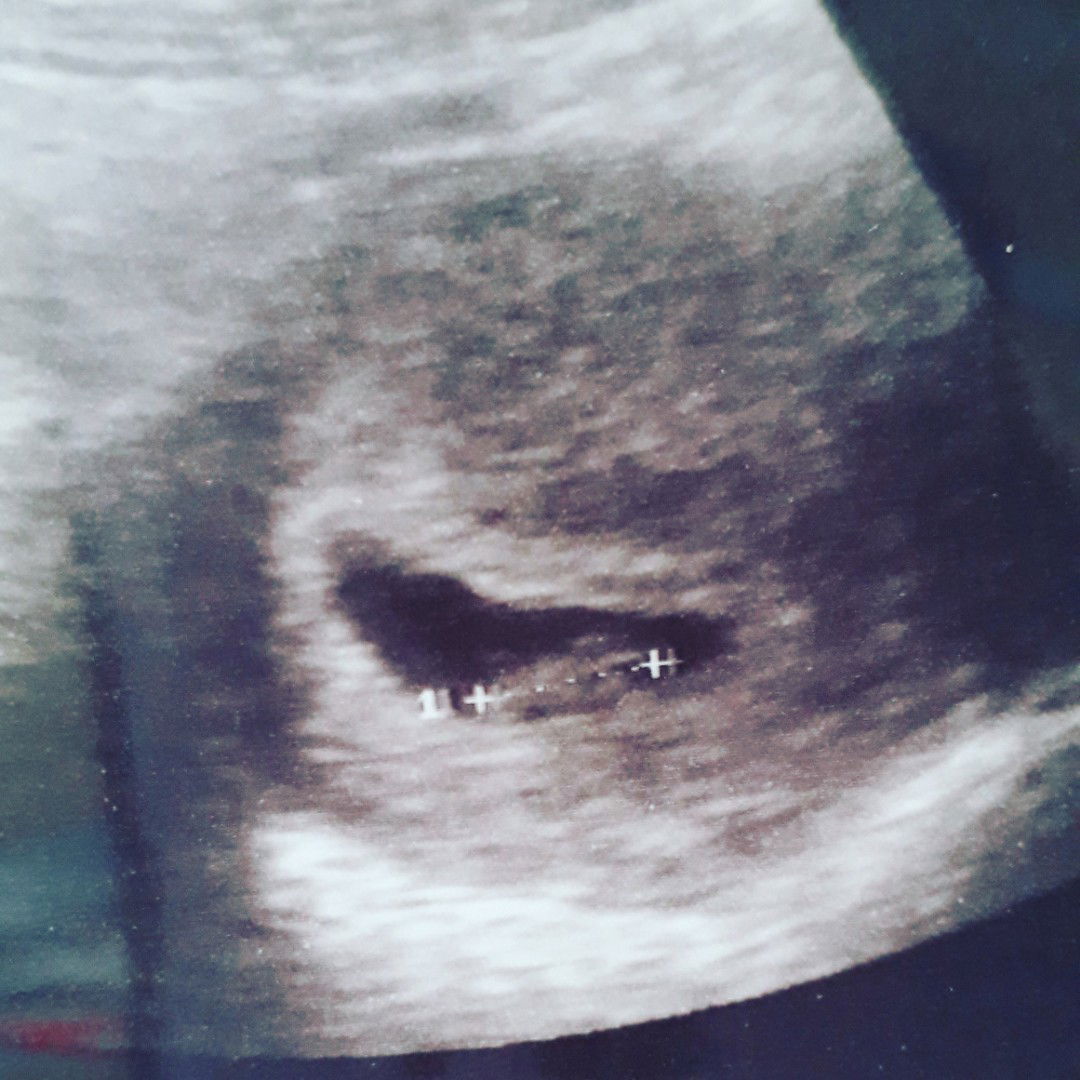

baby 10 weeks today..

Pergi spital scan slase lps time tu 9w6d doc scan baby kecik lg..x nmpk lg jantng..just nmpk kedip2 je..last priod 19/6 due klinik desa bg 26/3/2020..tp g kk doc bgthu due tu x tepat sbb x nmpk jntng lg..kne repeat lg 6 mnggu..hrp2 nmpk jelas lah jntng bby nnti..aminn mybe bln 4 jugak due tu..period sy x regular..